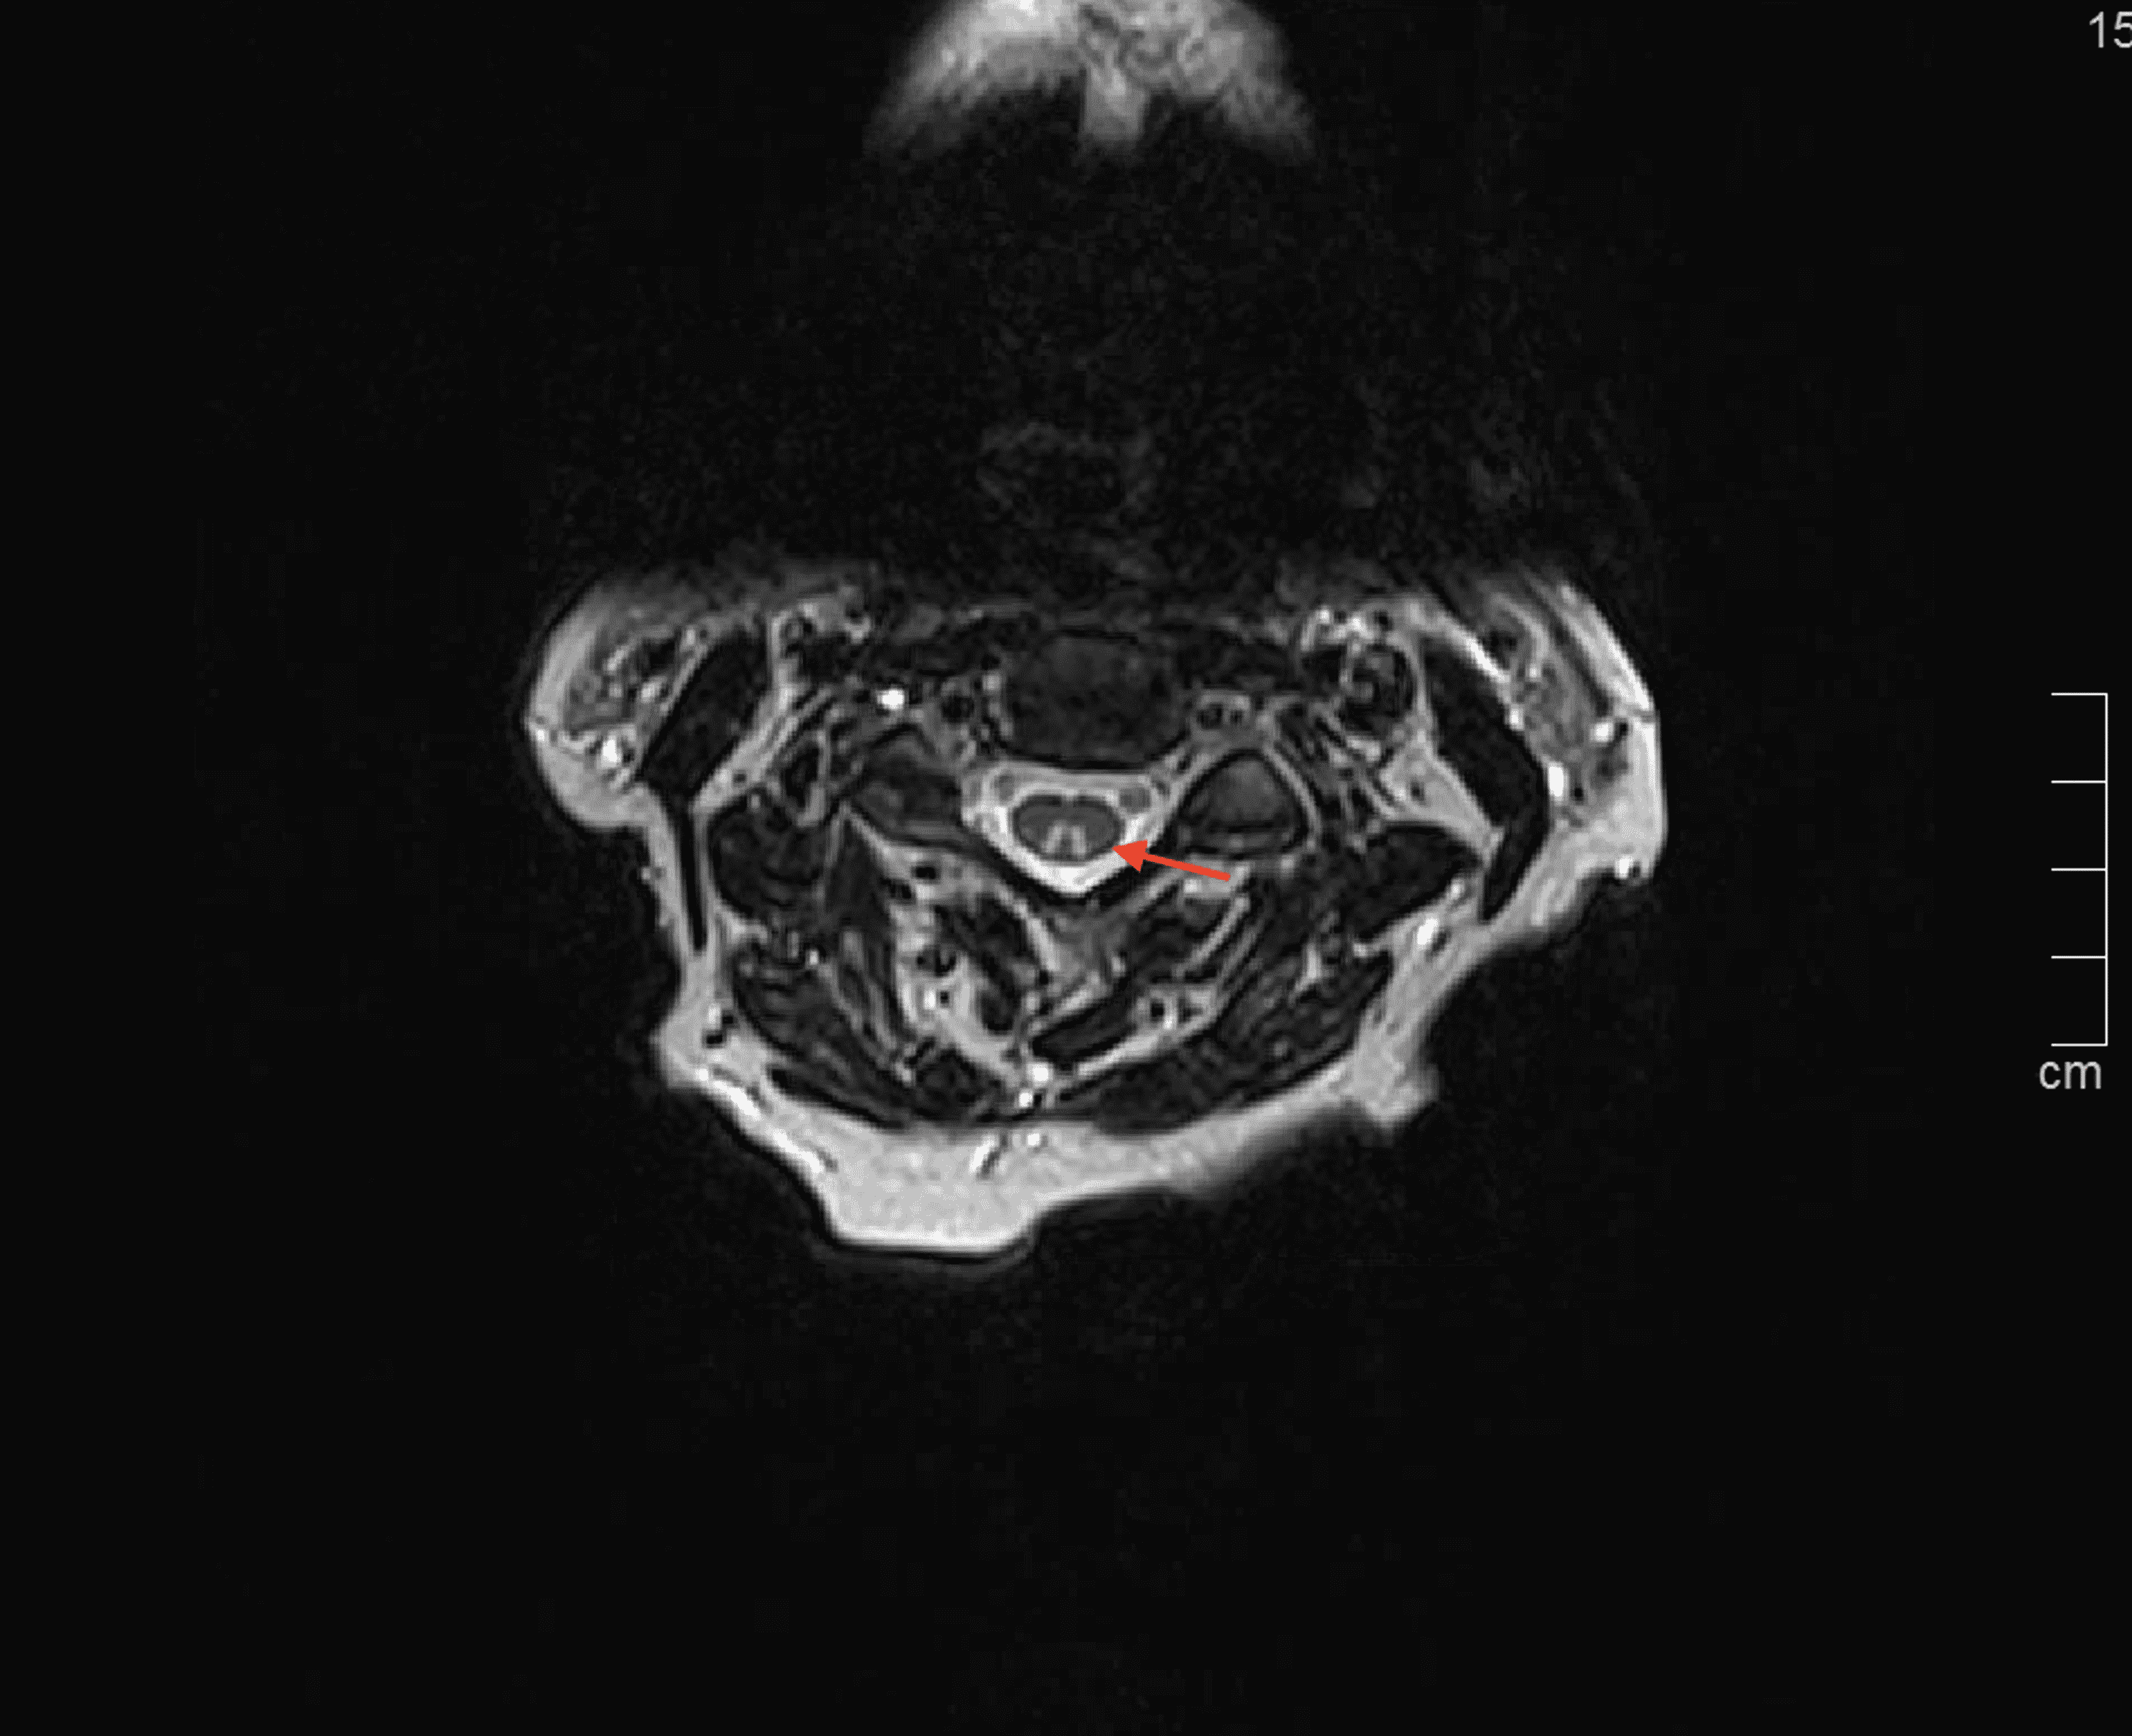

Cureus Copper Deficiency Myeloneuropathy Following RouxenY Gastric Copper Deficiency Roux En Y copper deficiency can cause hematological abnormalities with or without neurological complications. this clinical observation describes a patient who experienced gait disturbances, lower extremity weakness, and neuropathy. overall, copper deficiency occurs infrequently with bariatric surgery. Procedures that are both restrictive and. Copper Deficiency Roux En Y.

Cureus Copper Deficiency Myeloneuropathy Following RouxenY Gastric Copper Deficiency Roux En Y overall, copper deficiency occurs infrequently with bariatric surgery. Procedures that are both restrictive and. this clinical observation describes a patient who experienced gait disturbances, lower extremity weakness, and neuropathy. copper deficiency can cause hematological abnormalities with or without neurological complications. Copper Deficiency Roux En Y.